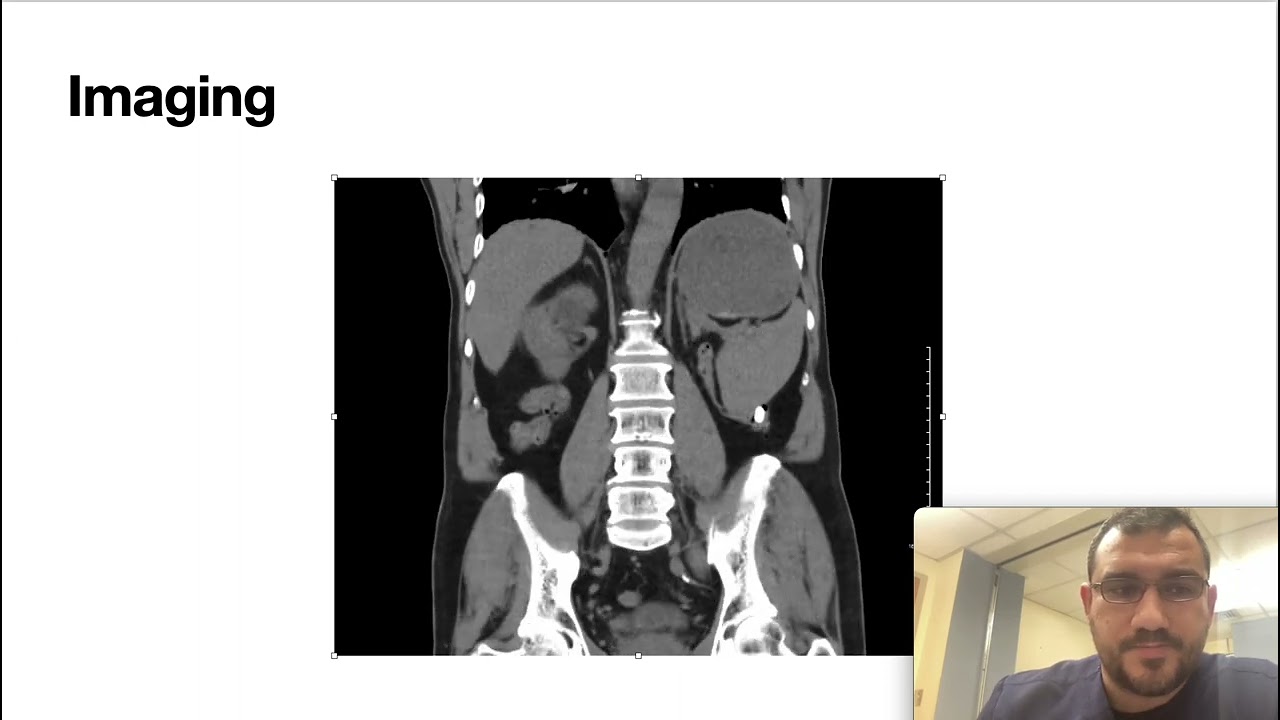

Internal Medicine Quick Cases-1 (Gastric outlet obstruction)

Описание: In this video, I presented a case of gastric outlet obstruction.